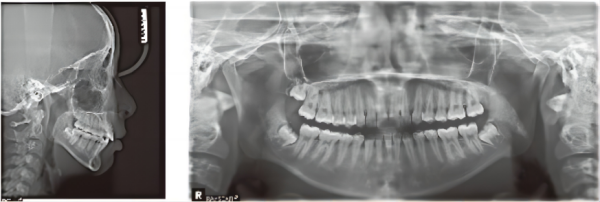

X線

混雑は緩和され、Spee curvEは平準化される。 両側臼歯と犬歯の間には中立的な関係があり、深いオーバーバイトが修正されています。

顔のプロファイルは、対流性が低下すると改善され、あごの位置は安定しています。 笑顔の写真に顕著な改善があります。

1. MolarのdistalizationはVinciSmileの処置の主要な利点です。 この場合、患者は上顎の親知らずを抜こうとはしないため、遠位運動が制限されます。